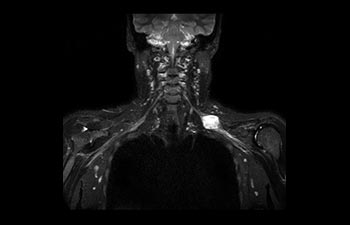

Brachial Plexus lesion